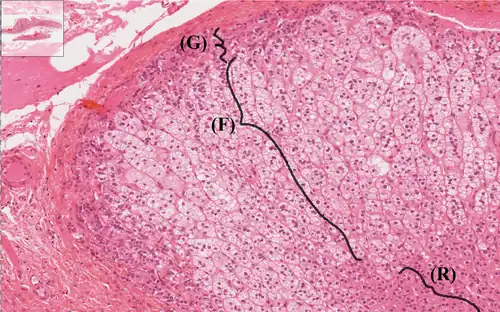

Le cortex surrénal dérive du mésoderme[4]. Il est composé de cellules glandulaires endocrines à sécrétion lipidique divisé en trois zones qui se répartissent en trois couches successives :

Dans la couche distale du cortex surrénale se trouve la zone glomérulaire (G). Les cellules y sont organisées en îlots. Ils produisent des minéralocorticoïdes qui permettent la régulation du métabolisme des ions et des sels.

Dans la couche suivante se trouve la zone fasciculaire (F). Les cellules y sont organisées en cordons. Elles produisent les glucocorticoïdes (cortisone, hydrocortisone) qui ont une action anti-inflammatoire.

Dans la dernière couche du cortex surrénal, se trouve la zone réticulaire (R). Les cellules y sont organisées en îlots. Ils produisent l'androgène.

En microscopie optique, coloration de routine (Trichrome de Masson bleu, vert, etc.), coupe paraffine (extraction des lipides).